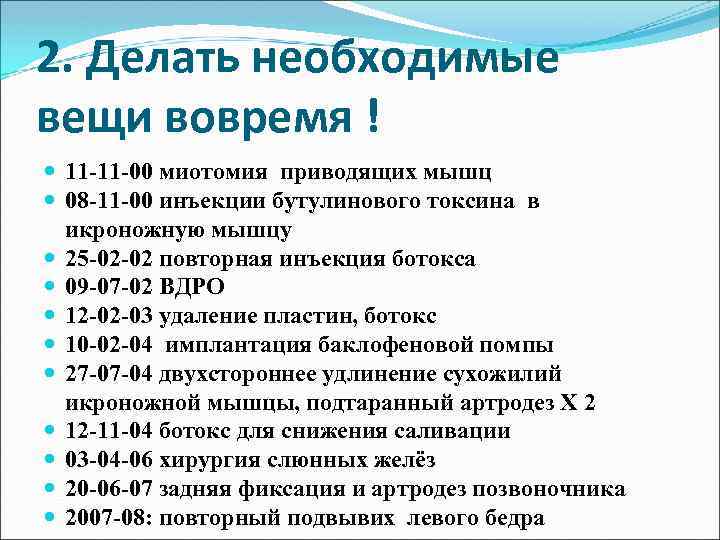

2. Делать необходимые вещи вовремя ! 11 -11 -00 миотомия приводящих мышц 08 -11 -00 инъекции бутулинового токсина в икроножную мышцу 25 -02 -02 повторная инъекция ботокса 09 -07 -02 ВДРО 12 -02 -03 удаление пластин, ботокс 10 -02 -04 имплантация баклофеновой помпы 27 -07 -04 двухстороннее удлинение сухожилий икроножной мышцы, подтаранный артродез Х 2 12 -11 -04 ботокс для снижения саливации 03 -04 -06 хирургия слюнных желёз 20 -06 -07 задняя фиксация и артродез позвоночника 2007 -08: повторный подвывих левого бедра